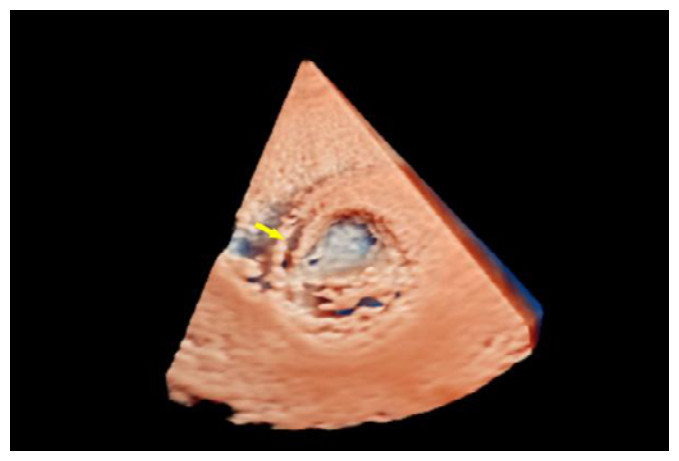

辅助检查如下。实验室检查:高敏C反应蛋白(hs-CRP)和红细胞沉降率(erythrocyte sedimentation rate, ESR)轻度升高。心电图:正常窦性心律,无ST段异常改变。胸部CT:双侧肺门中心对称分布的斑片状高密度影,部分实变,伴空气支气管征,病变边缘模糊。超声心动图:二维超声(2D)主动脉短轴切面显示右乏氏窦瘤破裂(ruptured of ASV, RASV),破入右心房形成“囊袋状”结构,长约1.7 cm,基底部破口内径约0.8 cm(图 1A)。彩色多普勒(color Doppler flow imaging, CDFI)显示全心动周期的左向右分流(图 1B)。连续多普勒(continuous doppler, CW)测得连续分流。室间隔内见4.0 cm×0.7 cm无回声区(图 2A),CDFI显示彩色血流信号随心动周期进出该无回声区(图 2B),考虑室间隔夹层瘤(dissecting aneurysm of the interventricular septum, DAIS)。实时双平面成像同步显示窦瘤破口与室间隔夹层相延续。应用Philips TrueVue三维(three-dimensional, 3D)超声心动图成像模式直观展示室间隔夹层瘤的立体结构(图 3)。

| 图 3 3D超声显示左室短轴切面室间隔夹层动脉瘤立体结构 |

在诊断方式的选择与鉴别上,超声心动图是RASV诊断的核心手段。二维超声可清晰显示窦瘤形态、破口大小及室间隔夹层范围,CDFI可评估RASV所引起的全心动周期血流动力学改变,观察异常分流的方向、流量及面积。实时双平面成像是一种新型的三维超声心动图技术,同步验证了RASV和DAIS的解剖关联。True Vue心内成像技术是一种独特的3D超声心动图可视化方法,在显示3D立体图像的同时,虚拟光源可以在不同方向上移动,以模拟光通过组织的传播,从而获得类似于“外科手术”视角,能直观呈现病变立体结构,为手术方案制定提供精准依据。